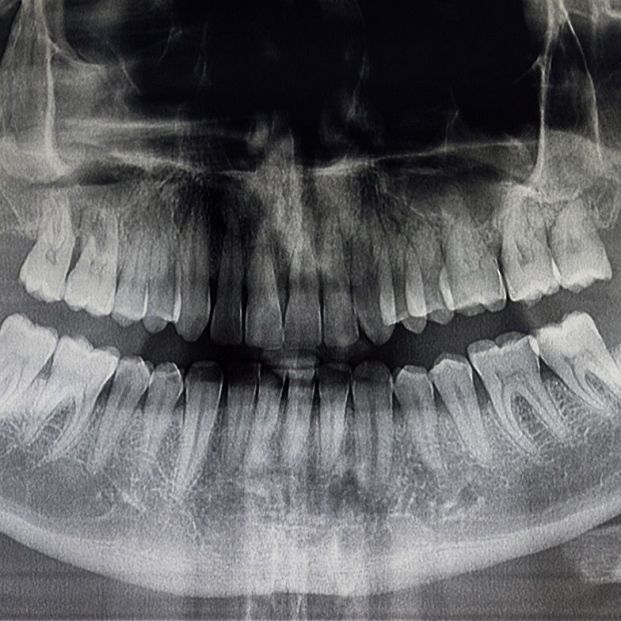

En caso de necesitar pruebas adicionales, puede solicitar una radiografía para ver con más claridad cómo se encuentra esta articulación.